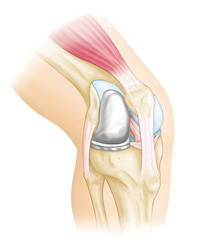

In unicompartmental knee replacement, only one area of the knee is resurfaced.

An advantage of partial knee replacement over total knee replacement is that healthy parts of the knee are preserved, which helps to maintain more "natural" function of the knee.

A partial knee replacement implant.